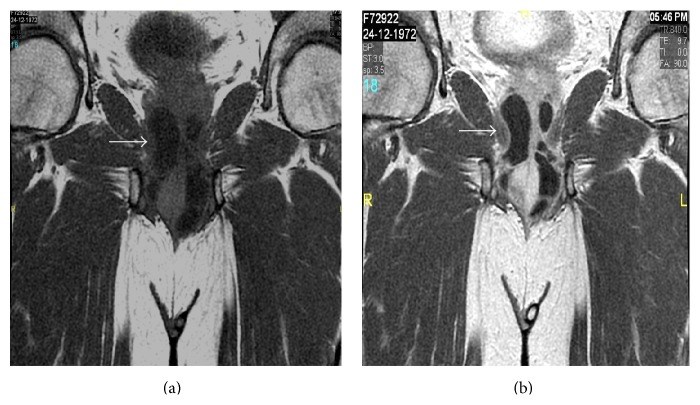

Cowper's gland syringocele is an uncommon, underdiagnosed cystic dilatation of Cowper's gland ducts showing various radiological patterns. Herein we report a rare case of giant Cowper's gland syringocele in an adult male patient, with description of MRI findings and management outcome.